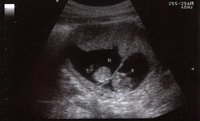

Las complicaciones en el embarazo y el parto causan muchas muertes de adolescentes

EmbarazoEn una reciente reunión el Comité Ejecutivo de la Organización Mundial de la Salud (OMS) ha puesto de manifiesto que las complicaciones en el embarazo y el parto son la primera causa de muerte de adolescentes de entre 15 y 19 años en los...